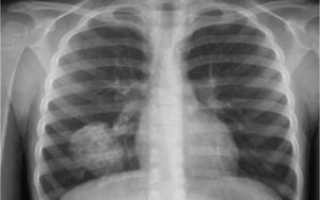

Рентген здоровых легких

Рентгенография лёгких представлена снимками в двух проекциях, на которых хорошо видны: лёгочная ткань, рёбра, ключицы, плечевой пояс, купола диафрагмы, сердечная тень и тени органов средостения, сосудистого пучка, позвоночного столба и грудины, которые накладываются друг на друга.

Для правильной расшифровки рентген-снимка важно знать: как на рентгенограмме выглядит норма. Лёгкие представляют собой воздушный орган. Даже незначительные затемнения, просветления или асимметрия лёгочного рисунка могут свидетельствовать о серьёзной патологии на ранней стадии развития.

- чёткость и контрастность рентгенограммы — определяется силой рентгеновских лучей, выбор режима «Худой», «Средний»,«Полный» делает врач. Основываясь на индивидуальных особенностях человека (при большей массе тела и выраженных жировых отложениях требуется увеличить дозу рентген-лучей для чёткого снимка), при помощи цифрового анализа возможно усиление или ослабление контрастности. Здоровые лёгкие (снимок позитив) Здоровые лёгкие (снимок негатив)